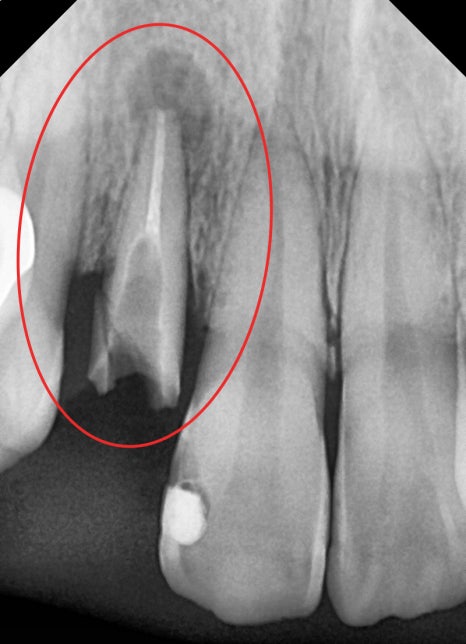

1. 치관 파절, 뿌리 끝 염증(Apical lesion) 발견

2. 잔존치근 발거

3. 발치와보존술 시행